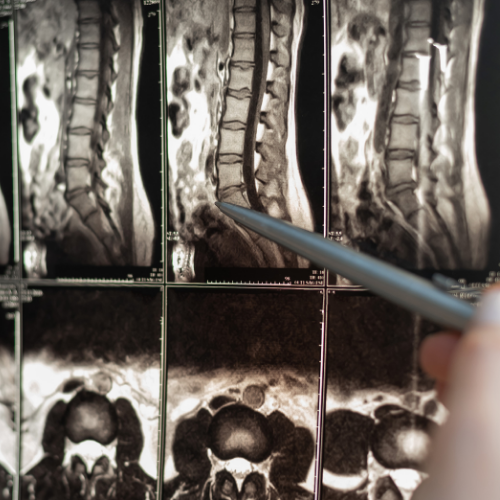

Belirtiler genellikle çocukluk veya genç yetişkinlik döneminde fark edilir ve kişiden kişiye büyük farklılıklar gösterir. En karakteristik semptom, özellikle öksürme, hapşırma, ıkınma veya başı aniden hareket ettirme gibi durumlarda şiddetlenen ense ve baş ağrısıdır. Bunun yanı sıra hastalarda denge kaybı, el becerilerinde azalma, kollarda ve bacaklarda uyuşma, yutma güçlüğü, görme bozuklukları ve uyku apnesi gibi nörolojik şikayetler gözlemlenebilir. Birçok vaka, başka bir nedenle çekilen MR (Emar) görüntülemeleri sırasında tesadüfen teşhis edilmektedir.

Tedavi süreci, semptomların şiddetine ve hastanın yaşam kalitesine olan etkisine göre planlanır. Ancak şiddetli ağrıların, belirli nörolojik defisitlerin veya sinir sistemi hasarı riskinin bulunduğu durumlarda cerrahi müdahale temel çözüm yoludur. "Posterior fossa dekompresyonu" adı verilen cerrahi işlemle kafatası tabanındaki basınç azaltılır, beyincik için daha fazla alan yaratılır ve beyin omurilik sıvısının normal akışı yeniden sağlanır. Erken teşhis, sinir sisteminde oluşabilecek kalıcı hasarların önlenmesi açısından kritik önem taşır.